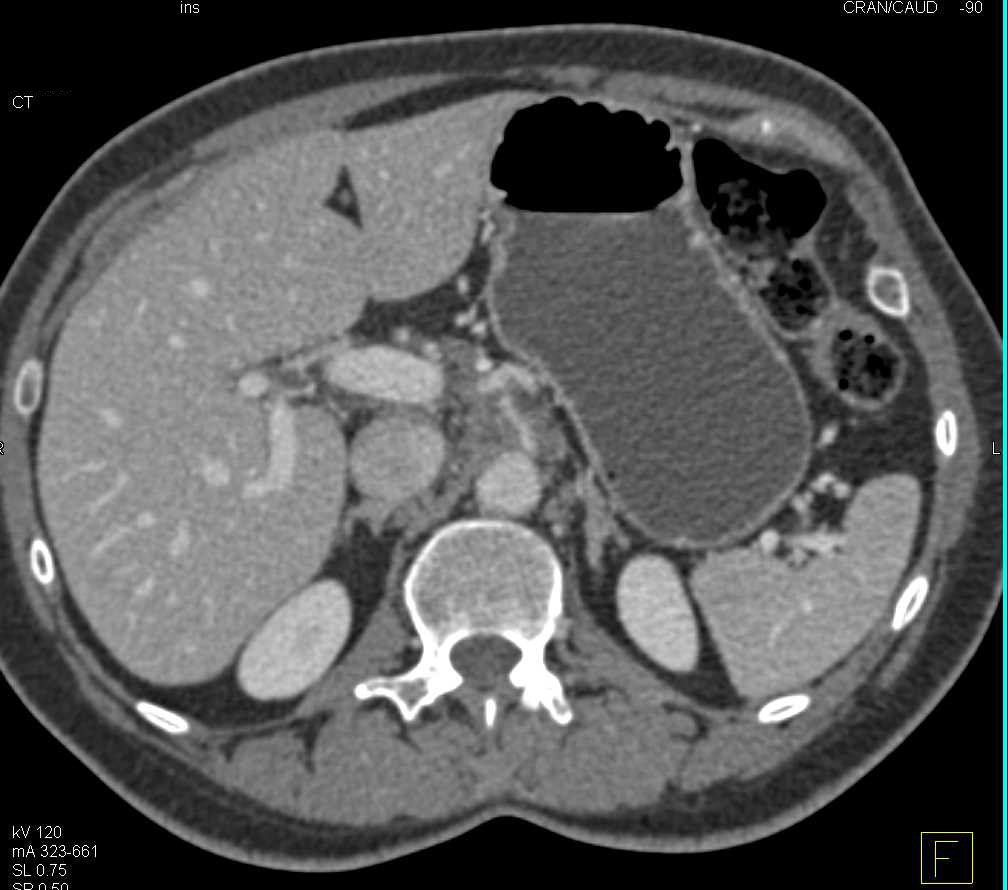

Pancreatic Cancer Encases the Celiac Artery